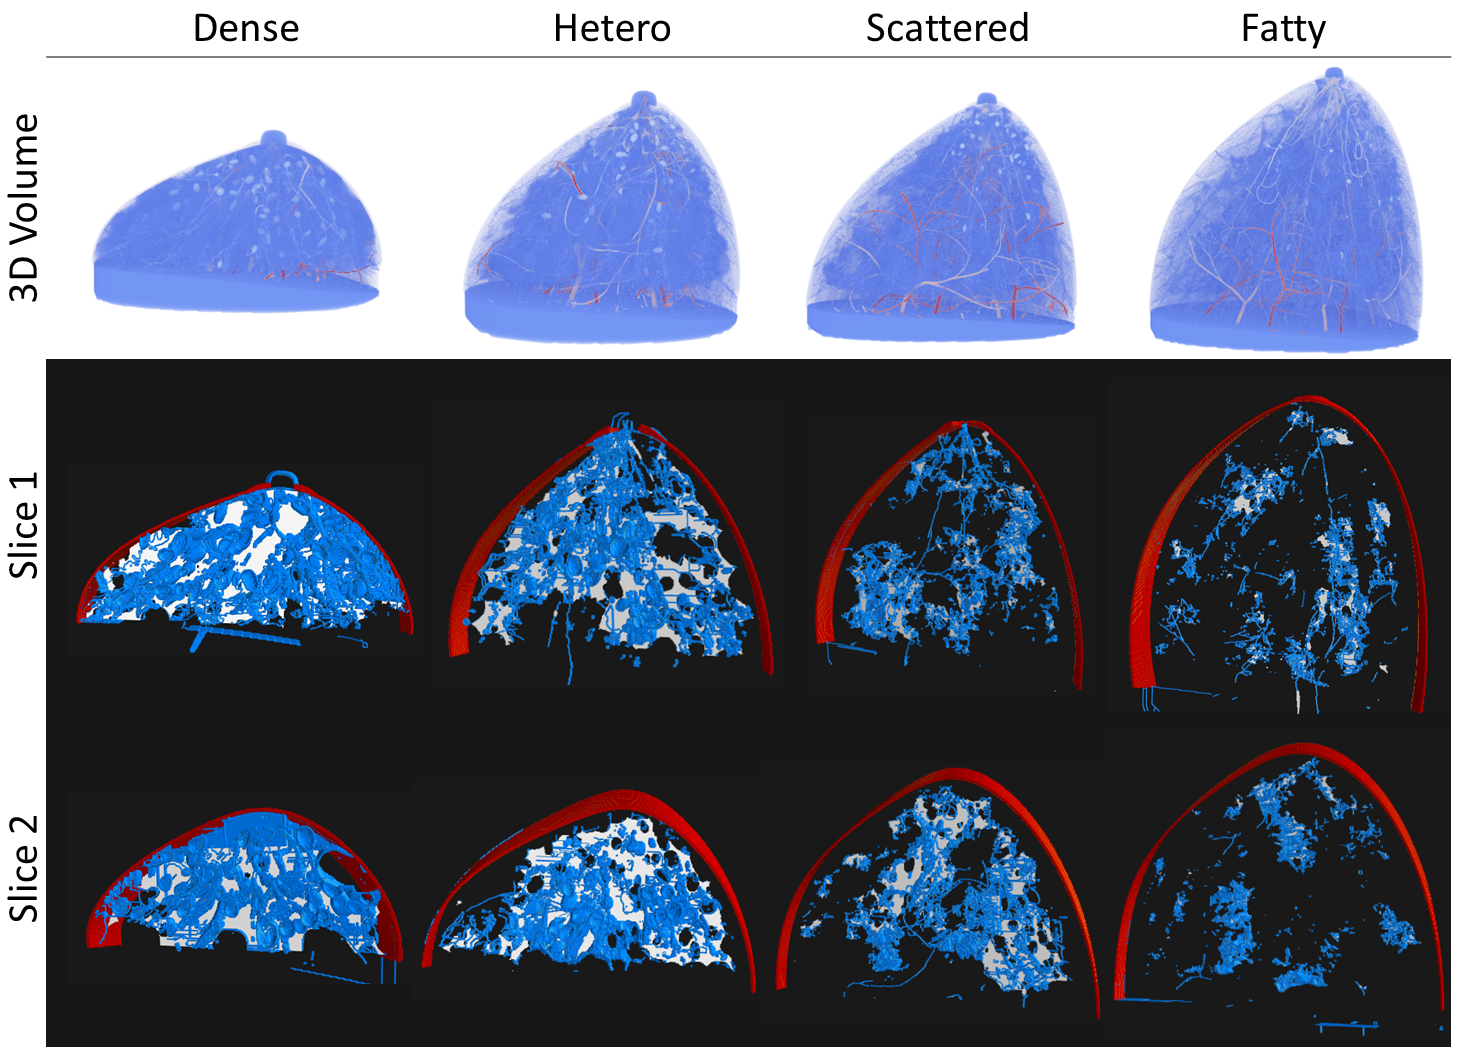

3.1 VICTRE synthetic dataset and the synthesized MRIs

The VICTRE Breast Phantom generates various types of synthesized breast image volumes based on tunable parameters. Here, we adopt the default configurations used in the VICTRE trial to generate four different profiles of breast phantom densities, covering different real world scenarios: dense, heterogeneously dense, scattered density, and fatty. A synthetic 3D breast phantom is a multi-class mapping in which each voxel is assigned with one of 10 tissue types: fat, skin, glandular, nipple, muscle, ligament, terminal duct lobular unit (TDLU), duct, artery, and vein. Table 1 summarizes the composition of tissue types for each profile. Figure 6 shows sample volumes for each of the four profiles. In experiments, we generate 25 sample volumes for each profile (100 in total) and simulate their corresponding MRIs for validation.

Using the 100 synthetic breast volumes, we perform simulations to generate 100 different synthetic T1-weighted MRIs. The T1/T2 weighted values for each tissue type are listed in Table 2. For each tissue type within a specific breast volume, we sample a single value for both T1 and T2. This ensures that all voxels associated with that particular tissue type have identical values within that breast volume. However, for different breast volumes, we derive a new set of T1 and T2 values for each tissue type based on the known distribution. The simulated MRI signal is then computed using:

where is the spin density, stands for the flip angle, and TR (repetition time), and TE (echo time) are MR acquisition parameters. In our experiments, we set , , ms, and ms to mimic different T1-weighted images. The simulated MR images are processed by our algorithm to extract topological structures. These extracted structures will then be compared with the ground truth tissues, specifically the synthesized breast image volumes. Figure 6 shows the corresponding MRI images of the four phantom volumes.

The topological precision and recall results are presented in Table 3. Our experiment was conducted on a total of 100 volumes, comprising 25 volumes for each breast profile. We report the outcomes for these different profiles, providing both the mean and standard deviation. The topological precision numbers indicate that the majority of the extracted topological mask resides within the true breast tissues, showing over 93% alignment for all four profiles. This high percentage demonstrates the accuracy of the extracted topological mask in delineating the actual tissue. Regarding topological recall, the extracted topological mask’s one-voxel thickness means it covers only a portion of the true tissue. In essence, the topological mask acts as a ’skeleton’ of the breast tissue. This observation is highlighted by the topological recall of 26.28% for dense breast profile. For heterogeneous, scattered, and fatty breast profiles, where the tissue is much sparser, the topological recall shows a lower percentage, ranging between 17% and 20%.

Similar observations are noted in the two distance-based metrics presented in Table 4. The low mean distance from tissue to topological mask, consistent across all profiles, indicates that the topological mask effectively covers the tissue, with a topological mask voxel usually in close proximity to any tissue voxel. Regarding the distance from topological mask to tissue, we observe low values for dense and heterogeneous profiles, suggesting that the topological mask closely approximates the true tissue in these profiles. Conversely, for scattered and fatty breast profiles, this distance is larger, implying that in these profiles, where the tissue is much sparser, the topological structures tend to be over-predicted, leading to false positive structures that are far from the actual tissue.

Qualitative validation. Figure 6 illustrates how topological structures effectively capture breast tissues. The first row presents 3D renderings of VICTRE-generated synthetic breast phantoms for four distinct profiles. The second and third rows display two slices at different positions of the corresponding breast phantoms, where the topological mask (in blue) and ground truth breast tissues (in white) are shown, alongside the breast outlines (in red). It is important to note that each slice’s rendering includes several additional slices around the target cross sections for detailed examination. It is clear that the blue topological structures closely match the white breast tissues, especially noticeable in the scattered and fatty volumes. This observation highlights that our extracted topological masks effectively mirror the actual breast tissues, confirming the biological significance of these structures.